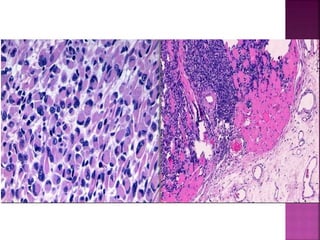

Rabdomiosarcoma.

 Sarcoma de partes blandas más frecuentes en la infancia y

adolescencia.

 Son más frecuentes en la cabeza y el cuello o el aparato

genitourinario.

 Los rabdomiosarcomas son neoplasias agresivas.

 El rabdomioblasto es la célula diagnóstica en todos los tipos.

Existen 3 subtipos histológicos:

 Se observan estrías transversales a la microcopia óptica (strap

cell)

 Rabdomiosarcoma Embrionario